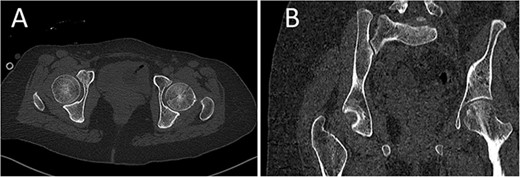

A medically free 42-year female presented to our institute as a life-saving case from a different hospital as she was a victim of unrestrained road traffic accident 2 days prior to presentation. Upon assessment in the emergency department (ER), she was conscious and oriented, and was found to have bilateral lung contusion, and multiple fractures of ribs. She also had a left sided vertical femoral head fracture dislocation comprising around 40% of the femoral head (Fig. 1). Closed reduction under conscious sedation was done in the ER, which was successful based on post-reduction imaging studies (Fig. 2). Her chest injuries were treated with chest tube and observation for 10 days. During that time, discussion was made with the patient regarding her situation and conservative management was chosen by way of bed rest and continuation of skeletal traction for 4 weeks with serial radiographs in the hospital on a weekly basis after clearance of her chest injuries. Skeletal traction was discontinued and she was advised to continue bed to wheelchair mobilization for an additional 2 weeks. After 6-weeks from the injury, a Computed Tomography (CT) was done to the patient and revealed signs of fracture healing (Fig. 3). At 3-years after the injury, she was found to have full painless range of motion of the affected hip and has resumed her activity of daily living without any complaints and the images showed a symmetrical joint space of the hips (Fig. 4).

CT scan of the chest, abdomen, and pelvis showing axial (A) and coronal (B) cuts of a left sided Pipkin I fracture comprising large surface of the femoral head with posterior hip dislocation.

CT scan of the pelvis showing axial (A) and coronal (B) cuts at 6-week post-injury showing signs of healing of the left fractured femoral head with a concentric hip joint.